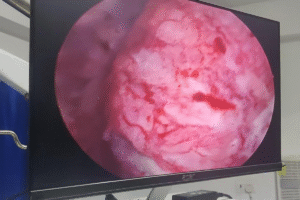

Latest Case Studies

Explore our latest urology case studies showcasing successful treatments, advanced surgical techniques, and patient recovery stories by expert urologists.